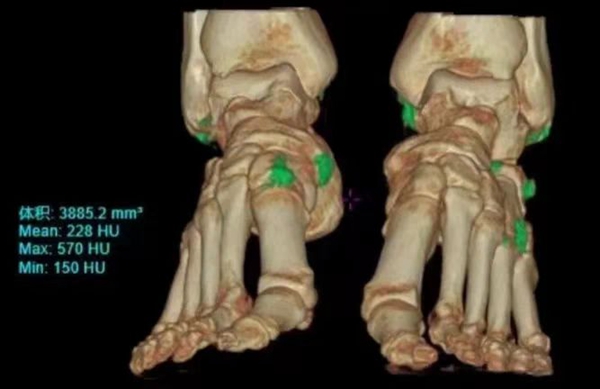

传统CT只能分辨物质密度差异,而能谱CT则可以识别物质成分差异,从而对疾病做出更准确的定性、定量分析。该设备支持16cm宽体能谱扫描,通过KV切换采集高低能数据,并根据不同物质不同能量下的衰减差异,获得组织中物质成分和能谱特征的定性及定量分析结果。常用于判定肿瘤的同源性、泌尿系结石成份分析、痛风石能谱成像等。

【痛风石能谱成像】